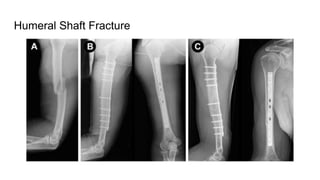

Humeral Shaft Fracture

Plating and Rush Nail Insertion